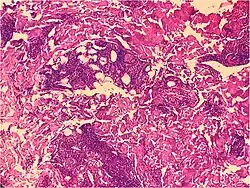

| Kaposi’s sarcoma in patch stage | The patch stage typically shows irregular proliferation of jagged vascular channels in the dermis below an integral epidermis. The so-called promontory sign is sometimes found in patch stage lesions and denotes vascular spaces surrounding pre-existing blood (see image).[23]

vessels |

|